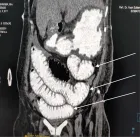

Intussusception is a leading cause of intestinal obstruction in young children, typically presenting with colicky abdominal pain and altered stool characteristics, before progressing to abdominal distension and bilious vomiting. This case report describes an 8-month-old male who presented with gastrointestinal symptoms, respiratory distress, and signs of intestinal obstruction. The patient was diagnosed with intussusception and found to be positive for Respiratory Syncytial Virus (RSV). After an attempted ultrasound-guided hydrostatic fluid enema, he underwent laparotomy to resolve the intussusception but developed post-operative complications, including delayed wound healing and wound dehiscence. The interplay of viral infections like RSV, and treatments such as steroids in pediatric surgical cases warrants further attention, especially concerning postoperative outcomes.